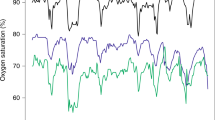

In the Bland–Altman plot, we found a low mean difference in SpO2 [−0.3 % points (95 % confidence interval −3.9 to 5.1), Limits of agreement (LoA)upper: 7.2 (CI 6.1 to 8.1), LoAlower −7.9 (CI −8.8 to −6.8)] with a low patient-weighted Spearman’s correlation between devices (r = 0.142). The HR showed a low mean difference [0.6 bpm (CI −0.85 to 2.05), LoAupper 5.6 (CI 5.2 to 5.9). LoAlower −4.4 (CI −4.8 to −4.0)] and a good correlation (r = 0.997). RR differed by −0.6 cycles (CI −3.9 to 5.1, LoAupper 8.0 (CI 7.2 to 8.6), LoAlower −6.8 (CI −7.4 to −6.0), with a moderate correlation (r = 0.586). The RMSE comparison was 4.2 points for SpO2, 4.0 points for RR, and 1.8 points for HR (Fig. 1; Table 2).

Bland–Altman plot and Spearman correlation for saturation (a), heart rate (b) and respiratory rate (c). The data is presented with a Bland–Altman plot (BA) and Spearman correlation between all measurements. In BA plot black lines represent mean and limits of agreement, grey areas describe the 95 % confidence intervals respectively